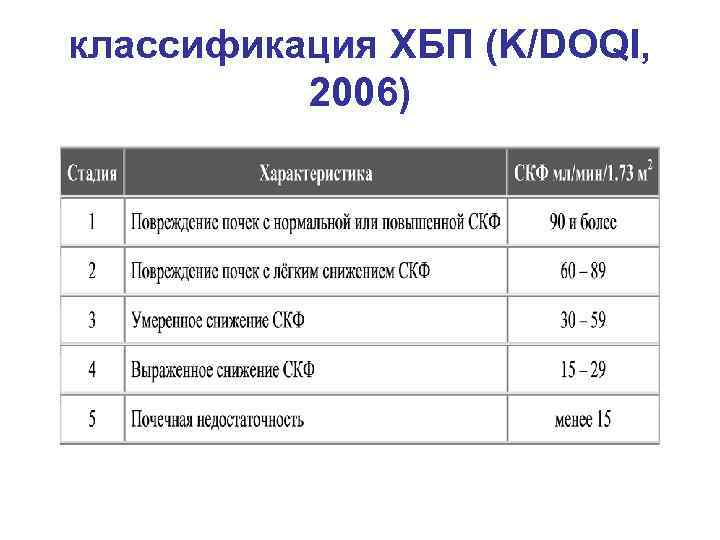

классификация ХБП (K/DOQI, 2006)

классификация ХБП (K/DOQI, 2006)

Значение СКФ < 60 мл/мин. (для диагностики ХБП) выбрано ввиду соответствия гибели более 50% нефронов. • Если признаков повреждения почек нет, а СКФ находится в диапазоне 60 -89 мл/мин. , то стадия ХБП не устанавливается. Данное состояние оценивается как снижение СКФ, что обязательно отражается в диагнозе. • У пожилых лиц (60 лет и старше) показатели СКФ в пределах 60– 89 мл/мин без инициирующих факторов риска ХБП расцениваются как возрастная норма.

Значение СКФ < 60 мл/мин. (для диагностики ХБП) выбрано ввиду соответствия гибели более 50% нефронов. • Если признаков повреждения почек нет, а СКФ находится в диапазоне 60 -89 мл/мин. , то стадия ХБП не устанавливается. Данное состояние оценивается как снижение СКФ, что обязательно отражается в диагнозе. • У пожилых лиц (60 лет и старше) показатели СКФ в пределах 60– 89 мл/мин без инициирующих факторов риска ХБП расцениваются как возрастная норма.